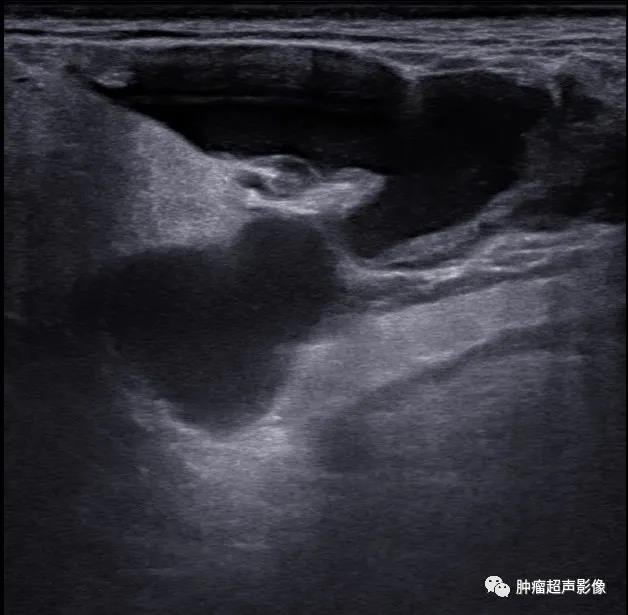

手术证实的口外型舌下腺囊肿:颌下腺周围不规则无回声向口底部延伸,边缘毛糙,无明确的包膜,透声佳,无血流。